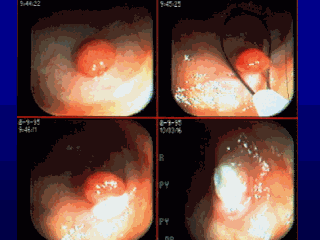

Adenomatous polyps, which are these little bumps that develop and can evolve into cancer, are very, very common. This is what I spend a fair amount of time doing: identifying polyps and removing them. These polyps are relatively common and are fairly simply removed, with a scar that heals up. Presumably, I am preventing cancer by doing this because I am taking out something that potentially could turn into cancer. There is data to support that.